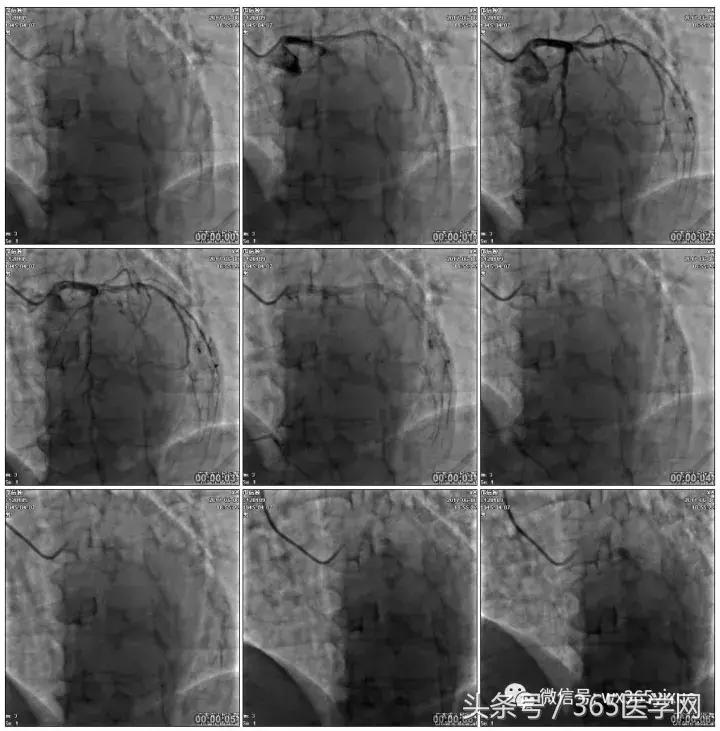

冠脉造影

基本资料

Syntax score 37.5

首先:IVUS指导下干预LAD

第二步:处理LCX

第三步:1月后

RRA:6F AL0.75 GC –RCA;

RFA:7F XB 3.5 GC—LCA 150cmcorsair

正向130cmFinecross微导管支持下尝试送PILOT150、Gaia 2导丝无法通过RCA闭塞段

SION导丝通过侧枝

逆向导丝:更换Gaia2

正向导丝:Gaia2,PILT150

正向导丝knuckle

2.5*15mm球囊扩张,逆向导丝尝试,但未能进入正向GC

1.正向2.5*15mm球囊扩张,Reverse CART

2.Guidezilla延长导管辅助下,逆向导丝进入正向GC

1.更换RG3导丝

2.GC送入普通导丝,保护LM

RCA闭塞段球囊扩张后IVUS

支架术后造影结果